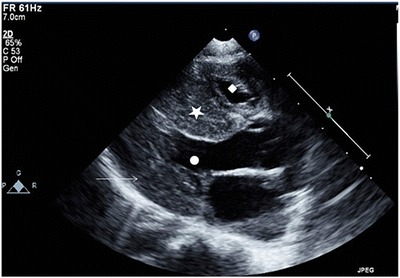

Antihypertensive treatment with amlodipine, captopril and intermittent nifedipine was initiated in addition to regular propranolol, which was continued. A repeat echocardiogram showed marked left ventricular hypertrophy, which had developed precipitously over 2 weeks since the previous echocardiogram (see Fig. 1).

Fig. 1.

Echocardiogram: parasternal long-axis view demonstrating septal (filled star) and left ventricular posterior wall thickening (arrow) with crowding of both the left (filled circle) and right ventricular cavity (filled diamond)

Hypertrophic cardiomyopathy has been previously associated with this mutation (Chol et al. 2003; Sudo et al. 2004; Wang et al. 2008). In one case this was transient; in a second case a change over time to a dilative type of cardiomyopathy was observed (Chol et al. 2003; Wang et al. 2008). The precipitous change in left ventricular morphology over the course of 2 weeks such as in this current case has also not been previously reported; no trigger such as a viral infection could be identified on routine testing to explain this acute presentation.